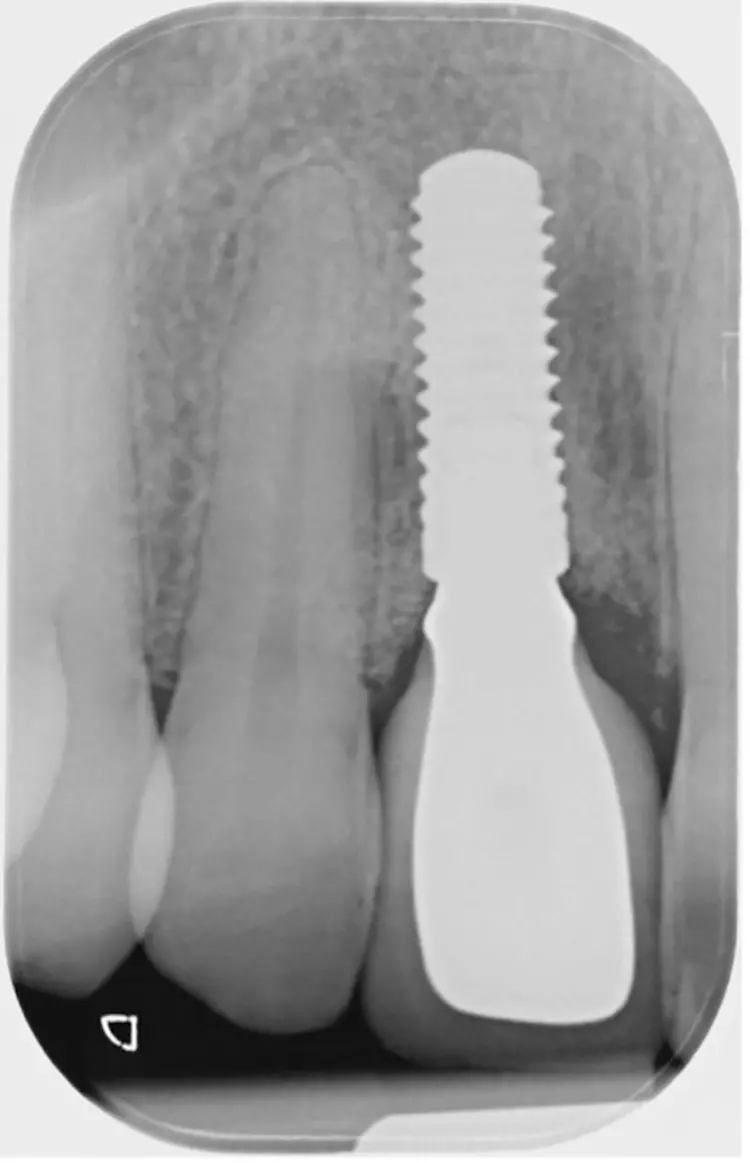

Auffällig war der Taschenbefund mit 9 mm bukkal und palatinal an Zahn 11, der auf eine Längsfraktur hindeutete. Im Rahmen der radiologischen Diagnostik wurde ein Orthopanthomogramm (Abb. 1) und ein Zahnfilm regio 11 (Abb. 2) erstellt mit sichtbarer periapikaler Aufhellung regio 11.

Nach einer viermonatigen Einheilzeit wurde im Rahmen der präimplantologischen Diagnostik ein DVT zur Überprüfung des Augmentationsergebnisses erstellt und die Implantatgröße festgelegt (Abb. 9 und 11). In Lokalanästhesie und unter Zuhilfenahme einer Bohrschablone erfolgte nach midkrestaler Schnittführung unter Schonung der Papillen die manuelle Insertion eines Straumann Bone Level Implantats mit den Maßen 4,1 x 10 mm RC (Straumann AG, Basel, Schweiz). Das Eindrehmoment betrug 35 Ncm.